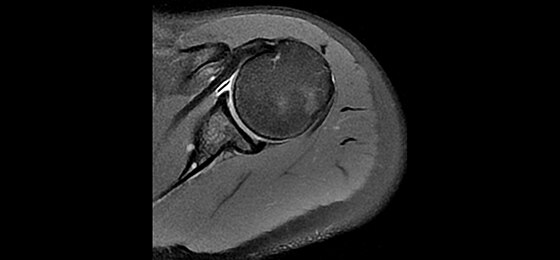

A large usable field of view is needed to properly image off-center anatomy such as a shoulder or hip. So the Discovery* MR750w features a 70 cm flared, open bore design with a large 50 x 50 x 50 cm field of view.

Gradients and RF body coils are water and air-cooled for optimum duty-cycle performance, short repetition time (TR) and echo time (TE), producing sharp and clear images.

Intuitive applications help clinicians utilize the full potential of 3.0T MR imaging.